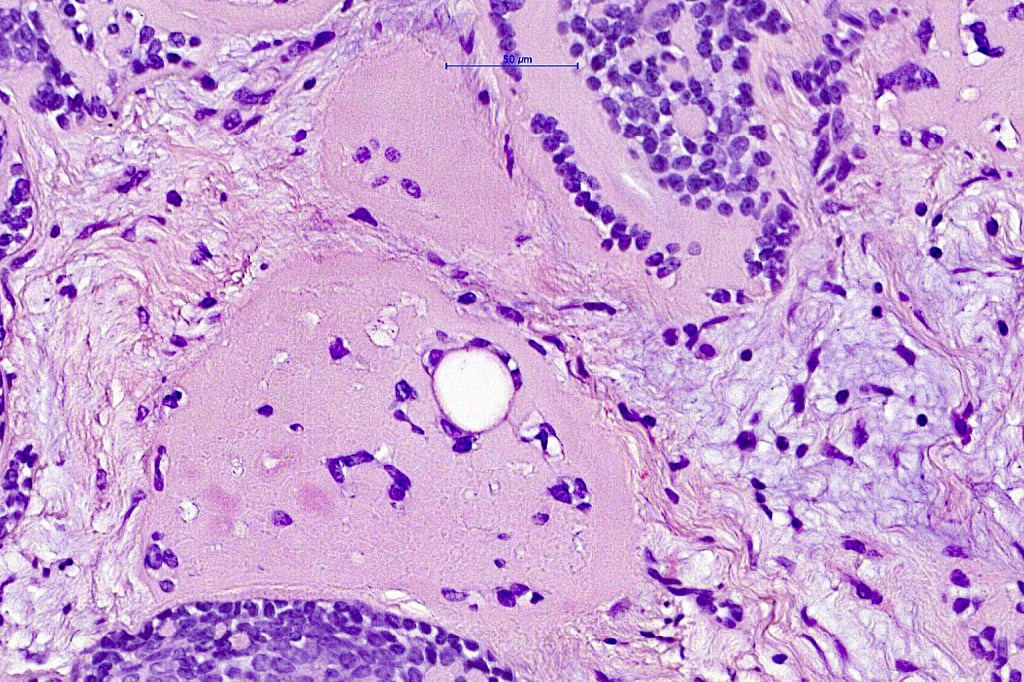

Histological features

•Dermal based

•Jigsaw/mosaic pattern arrangement of variably sized lobules of tumor cells with surrounding think, eosinophilic hyaline basement membrane

•Intralobular hyaline basement membrane material droplets

•Outer layer of intensely basophilic small cells surrounding larger central cells with pale staining or eosinophilic cytoplasm & vesicular nuclei

•Ductal differentiation